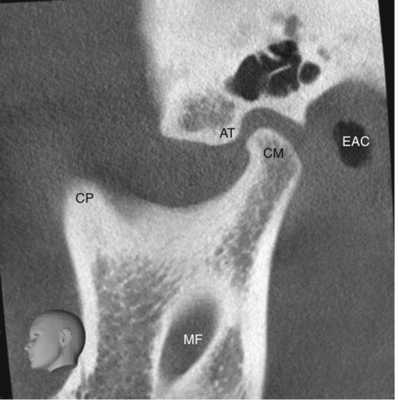

Височно-нижнечелюстной сустав (ВНЧС) — это синовиальный сустав, и он является единственный истинным суставом в челюстно-лицевой области. Он также известен как нижнечелюстной сустав, либо как черепно-нижнечелюстное сочленение. Височно-нижнечелюстной сустав является уникальным в связи с его вращательными (гинглимоидный сустав) и поступательными (артроидальный сустав) движениями во время функционирования нижней челюсти, включая открывание и закрывание рта, жевание и речь. Правый и левый суставы не могут двигаться независимо друг от друга, так как они соединяются через нижнюю челюсть, образуя двухмыщелковое сочленение (Alomar et al. 2007). Более того, зубы служат направлением и ограничивают определенные движения нижней челюсти. Как следует из названия, в образовании височно-нижнечелюстного сустава участвуют две кости, то есть височная кость и нижняя челюсть (Рисунок 1, 2, 3, и 4 ).

Рисунок 4 Сагиттальный срез конусно-лучевой компьютерной томографии височно-нижнечелюстного сустава у 22-летней женщины. АТ Суставной бугорок, СМ мыщелок нижней челюсти, СР венечный отросток, ЕАС наружный слуховой проход, МF отверстие нижней челюсти

Суставная ямка височно-нижнечелюстного сустава образована нижнечелюстной ямкой, медиолатерально вытянутой полостью, расположенной в нижней части височной кости непосредственно перед наружным слуховым проходом (Рисунок 5 и 6). Суставная ямка спереди ограничена костным выступом - суставным бугорком. Головка височно-нижнечелюстного сустава — это верхняя часть мыщелкового отростка, который является задней частью ветви нижней челюсти и расположена напротив ее передней части - венечного отростка.